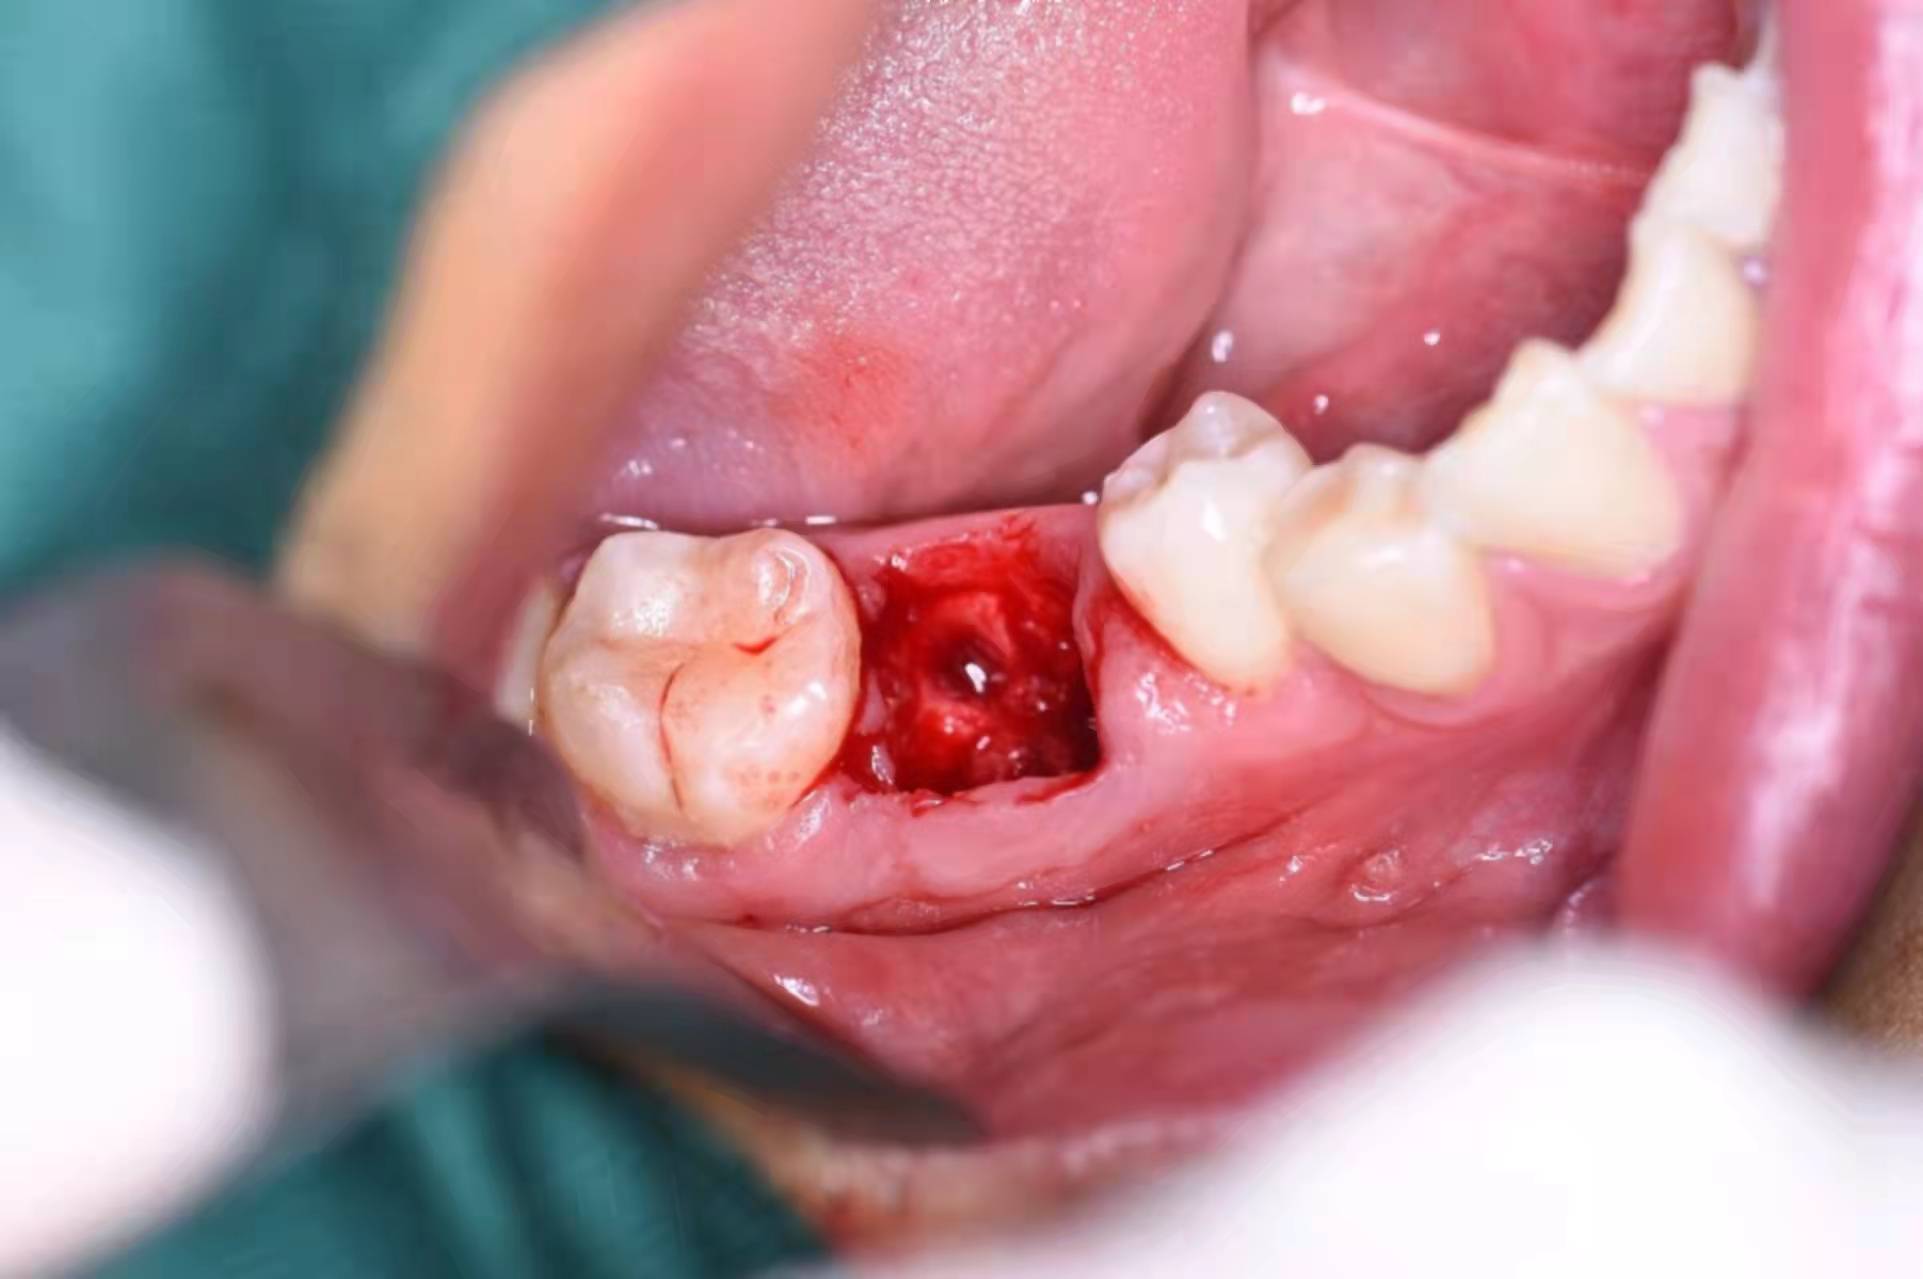

備洞,準(zhǔn)備植入種植體

植入種植體(諾貝爾)